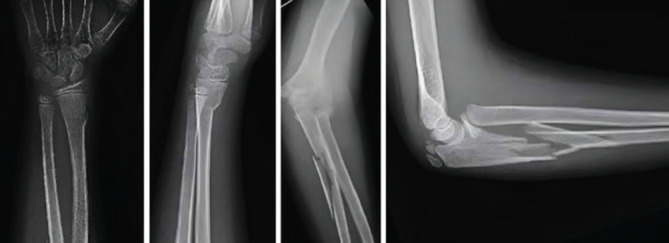

In this case report, we present a 13-years-old patient who sustained a Monteggia equivalent fracture along with an ipsilateral distal radius fracture following a fall on the elbow. Comminuted ulnar fracture was treated with open reduction and internal fixation with a bridging plate. After restoring the ulnar length, the radial neck fracture was successfully reduced. The distal radius fracture was managed conservatively. Our literature review shows that, the patient is one of the comparatively older patients treated with open reduction and internal fixation in this area and that a successful outcome was achieved with early mobilisation. This case underscores the need for further studies to determine the optimal treatment strategy in such cases.